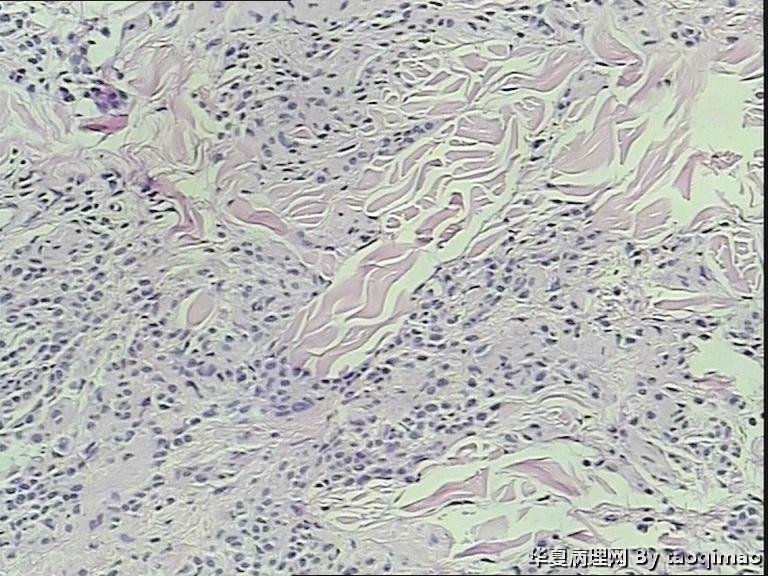

两例头皮肿物有差别么

34岁女,头皮肿物,带皮组织一块1x1,皮瓣上可见一灰白结节大小0.6x0.6,皮瓣大小1x0.4 面灰白质软。

门诊患者这一例没有其它更多信息

第一:皮内痣 第二:皮内痣并表皮囊肿

头皮皮内痣常呈皮赘样,质软有蒂,很多时候退化后呈正常肤色,切片中常有成熟的脂肪细胞,临床很容易误诊,诊断皮内痣应该没有问题的!

第二例合并的有个小的表皮样囊肿,或说粟丘疹。

灰白色,我想是由于有的皮内痣本身没有太多色素吧,不少皮内痣是皮色的。你的俩病例,片子里都没啥见到色素,应该可以解释了吧。